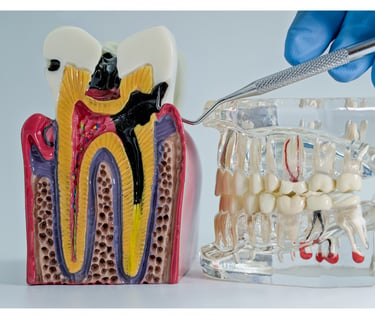

Endodoncia

Tratamos el interior del diente para eliminar el dolor y salvar la pieza dental